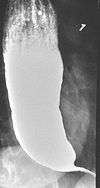

Barium swallow

The patient swallows a barium solution, with continuous fluoroscopy (X-ray recording) to observe the flow of the fluid through the esophagus. Normal peristaltic movement of the esophagus is not seen. There is acute tapering at the lower esophageal sphincter and narrowing at the gastro-esophageal junction, producing a "bird's beak" or "rat's tail" appearance. The esophagus above the narrowing is often dilated (enlarged) to varying degrees as the esophagus is gradually stretched over time.[5] An air-fluid margin is often seen over the barium column due to the lack of peristalsis. A five-minutes timed barium swallow can provide a useful benchmark to measure the effectiveness of treatment.